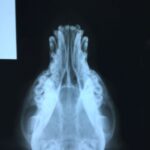

Chavela came in at the end of March- she was found with a large open wound which was exposing her skull. She suffered a skull fracture right above her right eye which healed on its own, and has had two surgeries to attempt to close the wound on her head. Her unusual eye expression is permanent is a result of the fracture and first surgery to pull her scalp together.